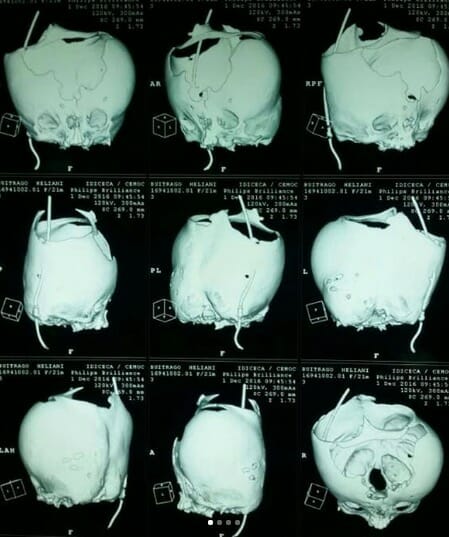

Läkarna meddelade tidigt att detta var en barn med många missbildningar: Lilla Helianny föddes med läppspalt, outvecklade ögon och med klumpfot och klumphand.

Helianny föddes också med hydrocefalus, vilket betyder att det finns mycket hjärnvätska i hjärnan.

Hjärnvätskan bildas i speciella hålrum inne i hjärnan och orsakar inte bara ett onormalt stort huvud.

Tillståndet kan också orsaka vävnadsskador på hjärnan.

”Jag skulle jämföra Heliannys utseende med en ”övernaturlig drottning”, eftersom hon har en krona inbäddad i huvudet. De ser lite ut som en drottningkrona. Jag såg hennes skönhet redan från första stund och det gör jag än idag”‚ säger mamman.